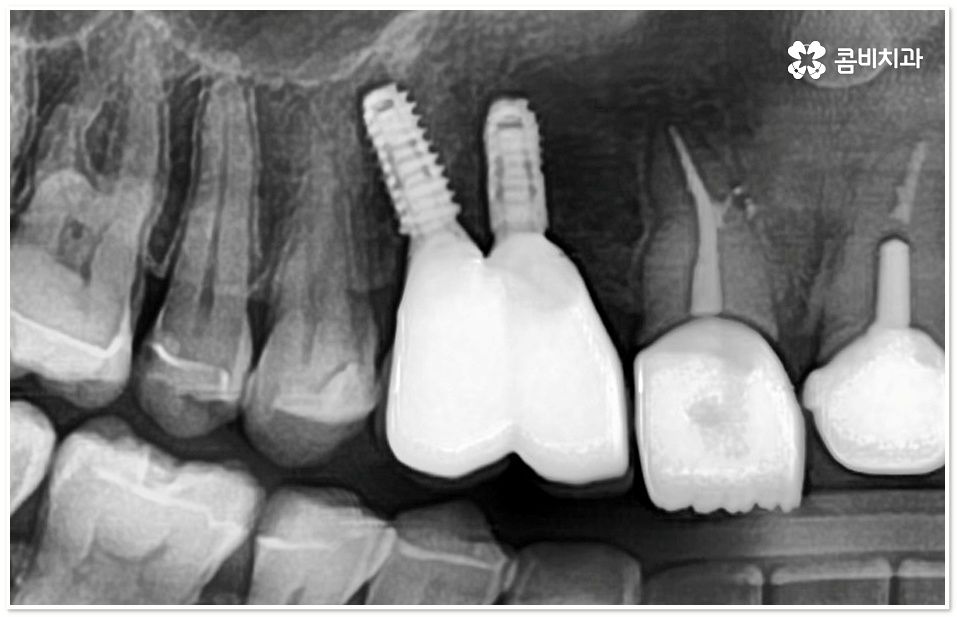

또한 앞니의 특성상 다른 치아보다 잇몸뼈가 얇고 폭이 좁으며 치조골 흡수가 잘 일어나기 때문에 환자분들의 상황에 따라서 잇몸뼈를 인공적으로 보충해야 하는 경우도 발생하는데, 이렇게 뼈이식 시술을 더하게 되면 치조골이 안정될 때까지 기다려서 식립을 진행해야 하기 때문에 보통 3개월 정도 걸리는 기간이 6개월 이상 늘어날 수도 있음을 감안하실 필요가 있습니다.

잇몸이 건강하고 치조골도 풍부하다면 치아를 발치한 후 바로 임플란트를 식립할 수 있지만 그렇지 않다면 식립 성공률이나 지속률을 높이기 위해서 뼈이식을 통해 바탕이 되는 부분을 충분하게 보충해 주는 것이 필요하므로 환자분들의 상황에 따라 앞니임플란트 시술 계획을 섬세하게 수립할 필요가 있어요.